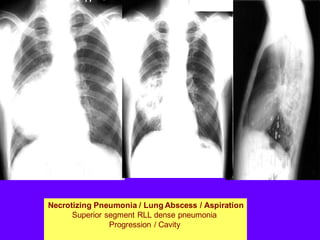

Necrotizing Pneumonia / Lung Abscess / Aspiration

Superior segment RLL dense pneumonia

Progression / Cavity